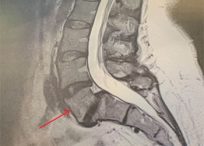

William J. Sonstein, M.D., F.A.C.S. is a Board-Certified Diplomate, American Board of Neurosurgery. He has a special interest in complex spine surgery and has one of the largest experiences with Posterior Lumbar Interbody Fusion (PLIF) on Long Island. This procedure relieves pain for patients with intractable back pain. Dr. Sonstein uses minimally invasive procedures whenever possible, such as Kyphoplasty and X-STOP™ to treat spinal compression fractures and spinal stenosis.

Case Studies